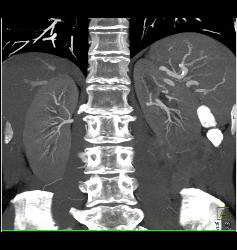

Renal Cell Carcinoma With Paraaortic Adenopathy